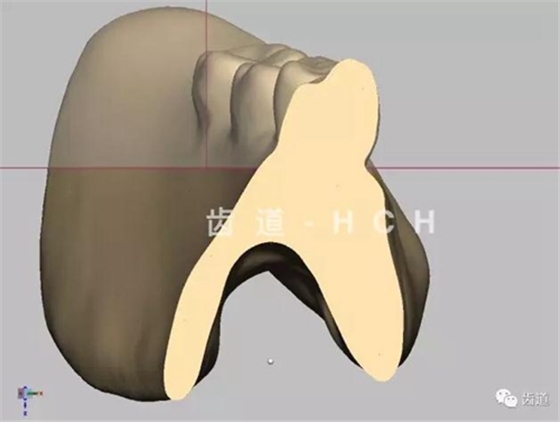

標(biāo)準(zhǔn)全口義齒模型截圖 科貿(mào)嘉友收錄